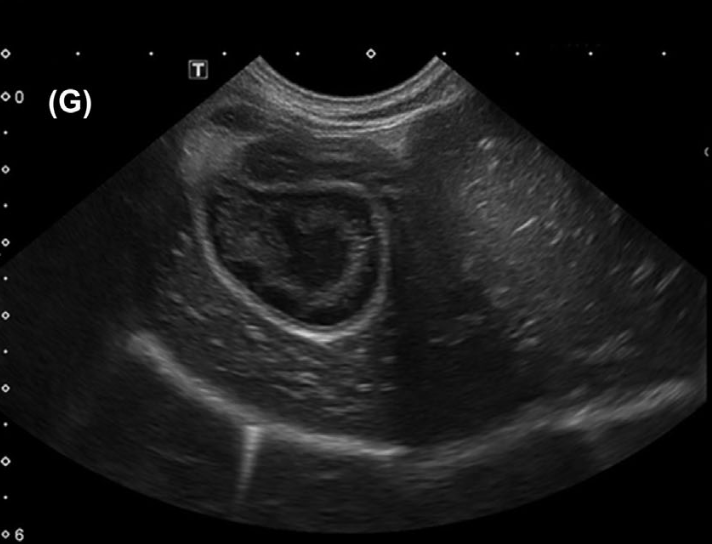

Печень является еще одним важным органом, который может быть поражен лептоспирами. Гистопатологические исследования выявляют холестатический гепатит с полным или частичным разрушением печеночной пластинки, гепатоцеллюлярный некроз, бинуклеацию гепатоцитов, перипортальный отек с острой и хронической воспалительной клеточной инфильтрацией и пролиферацией клеток Купфера вдоль синусоидальной выстилки10. Желтушная форма лептоспироза характеризуется более тяжелым и быстро прогрессирующим течением. В одном исследовании с участием 254 собак с острым лептоспирозом было установлено, что повышение уровня билирубина до 10 мкмоль/л и выше (реф. зн. 0,5–4,0 мкмоль/л) связано с неблагоприятным исходом (смерть или эвтаназия)14. Поражение печени может варьироваться от легкого повышения уровня печеночных ферментов с наличием или отсутствием гипербилирубинемии до тяжелой печеночной недостаточности с признаками энцефалопатии18. Повышение активности аланинаминотрансферазы (АЛТ), аспартатаминотрансферазы (АСТ) и щелочной фосфатазы (ЩФ), а также гипербилирубинемия чаще всего наблюдаются в сочетании с азотемией23. На данный момент не установлено, может ли Leptospira spp. выступать в качестве возбудителя хронического гепатита у собак, однако в литературе имеются данные о развитии мукоцеле желчного пузыря у собак с диагностированным лептоспирозом. В одном из исследований с участием 35 собак УЗИ-признаки мукоцеле были обнаружены у 9 животных (рис. 7)29.